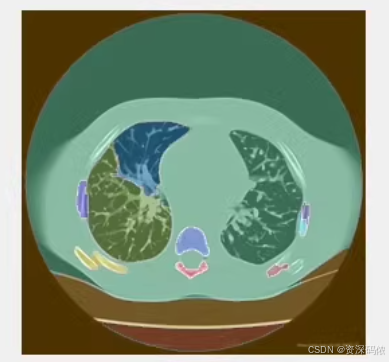

RGBLabels = label2rgb(L, 'jet', 'k', 'shuffle');

title('Final Segmentation with Watershed Algorithm');

% 在原图上叠加分割结果

title('Overlay of Original Image and Segmentation');